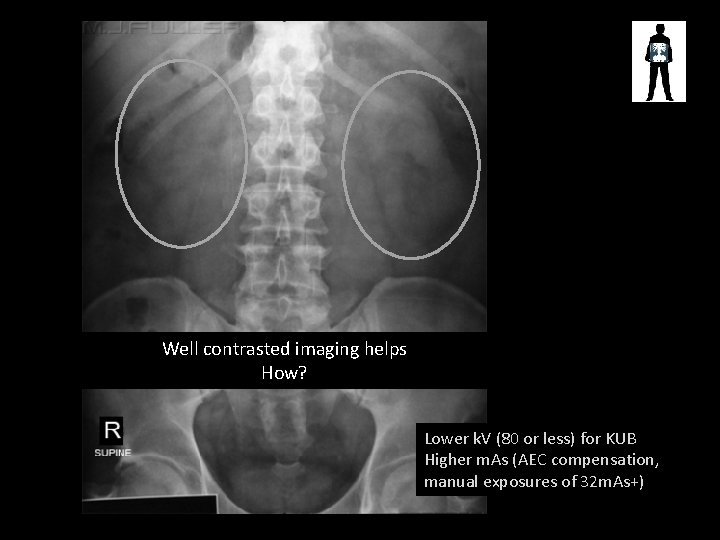

Can you see the renal areas?

Well contrasted imaging helps How? Lower k. V (80 or less) for KUB Higher m. As (AEC compensation, manual exposures of 32 m. As+)